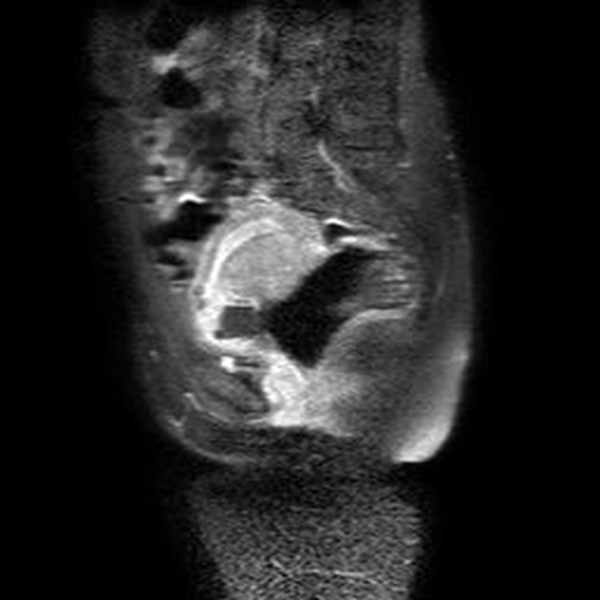

Se realizó una RNM (Philips 1.5 Tesla) que permitió confirmar el diagnóstico de EEC (figuras 5 a 8).

Figura 7A Imágenes de RMN potenciadas en T2 con supresión de la grasa. A) Plano axial y B) Plano coronal, donde se identifica el saco gestacional como una estructura quística con tejido fetoplacentario en su interior y localizado en el canal cervical

Figura 7B Imágenes de RMN potenciadas en T2 con supresión de la grasa. A) Plano axial y B) Plano coronal, donde se identifica el saco gestacional como una estructura quística con tejido fetoplacentario en su interior y localizado en el canal cervical